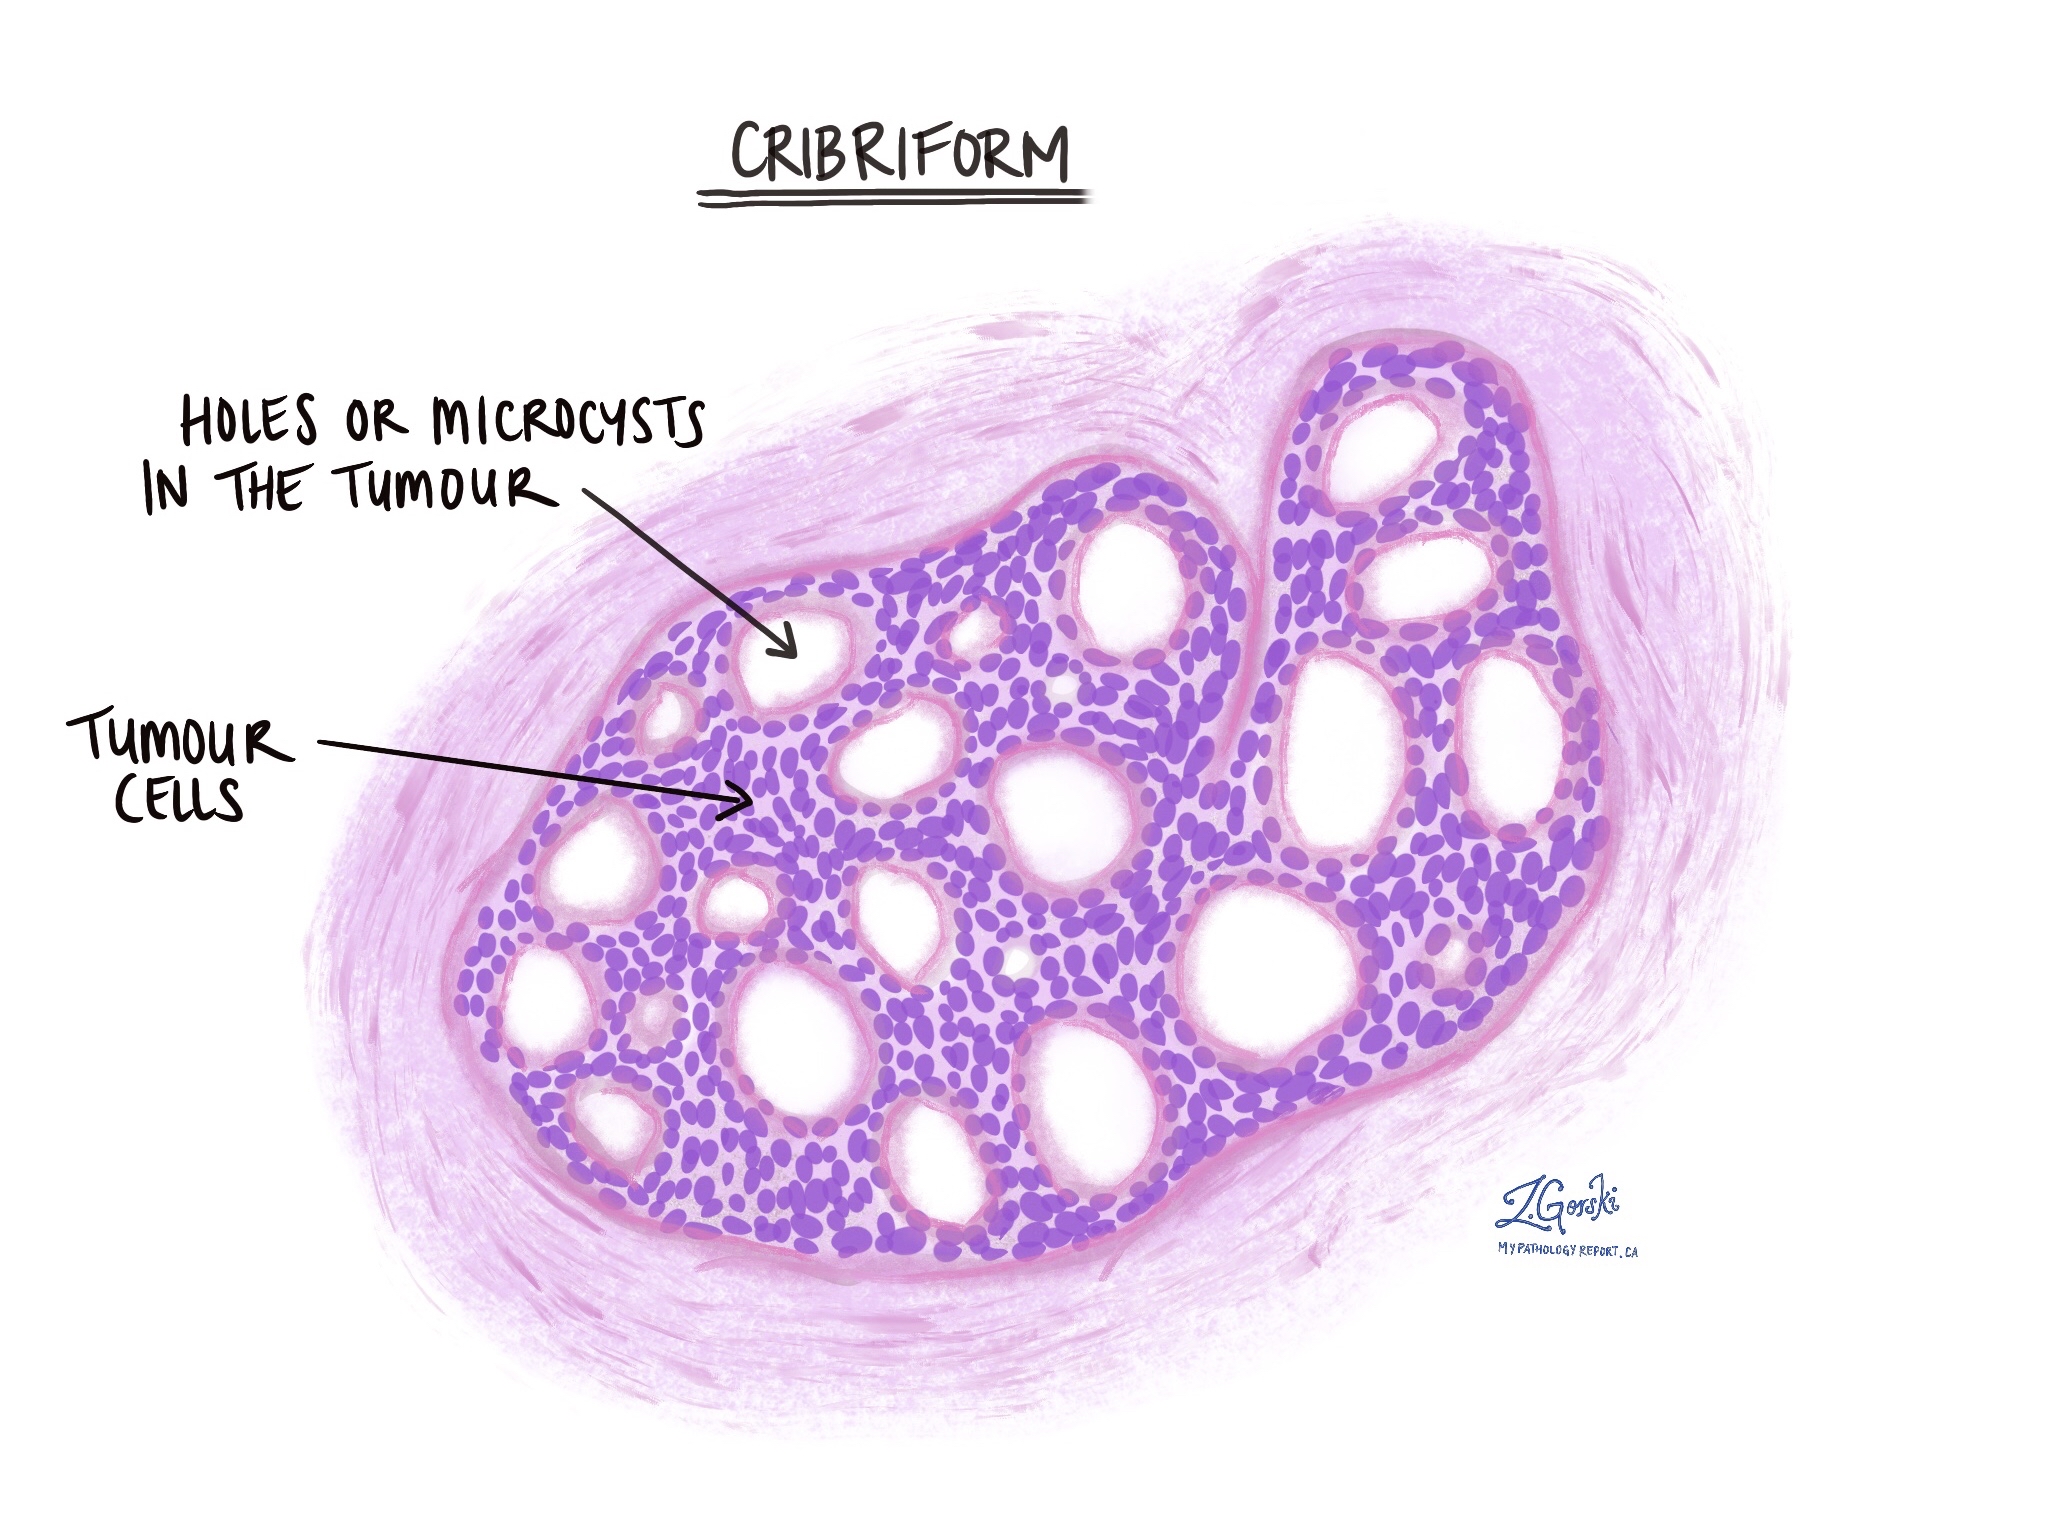

Раздел: Снимки-откровения